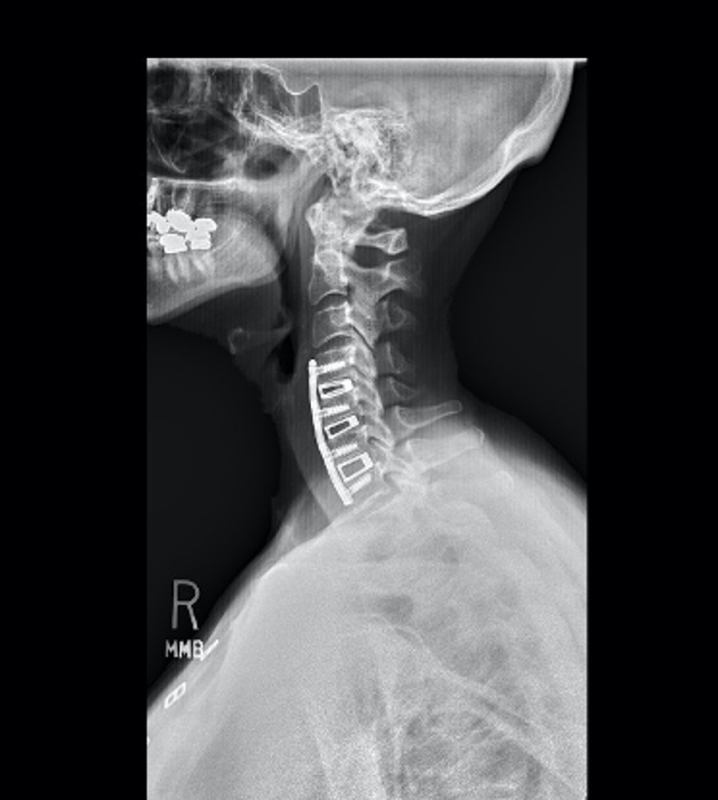

Her MRI did show disc herniations and bone spurs resulting in spinal canal stenosis. Her spinal cord was compressed, and on physical exam, she showed signs of a myelopathy. However, her cervical xrays showed a reversal of normal cervical stenosis and development of kyphosis. Given the mechanical degeneration in her cervical spine, a multilevel anterior fusion was recommended.

This lessened the structural stress on the adjacent segments, and alleviated her chronic neck pain. Pressure on the spinal cord was also corrected during the discectomies.